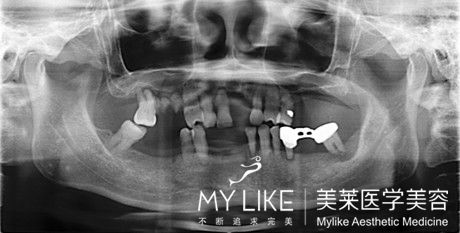

當(dāng)患者全口缺牙或即將拔牙后全口無牙,佳的處理方案就是進(jìn)行全口種植牙。與傳統(tǒng)的活動義齒相比,全口種植牙可以避免牙槽骨漸進(jìn)性萎縮的問題,而且種植牙無異物感,穩(wěn)定舒適,更可恢復(fù)咀嚼功能。

全口種植牙有兩種形式:

1、植入2-3顆牙種植體,起支持和固位的作用,制作全口覆蓋義齒,優(yōu)點(diǎn)是簡單、便宜。

2、植入4-6顆牙種植體,以種植體支持全口固定烤瓷牙,不需取戴烤瓷牙,舒適方便。 >>>全口牙種植的價(jià)格是多少?